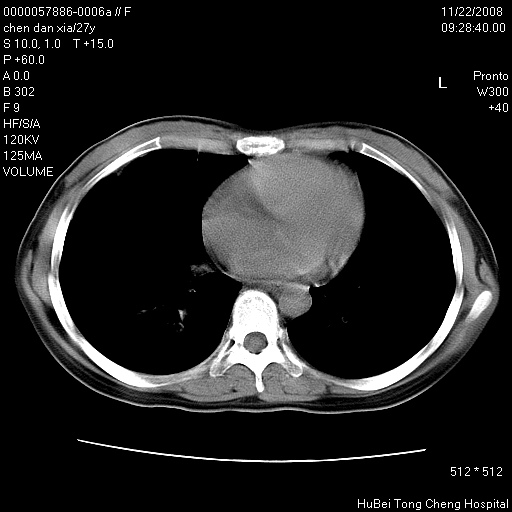

标题: CT16752:F,27Y。发热咳嗽20余天,伴盗汗。 [打印本页]

标题: CT16752:F,27Y。发热咳嗽20余天,伴盗汗。

气管前腔静脉后淋巴结肿大 右肺门纹理模糊

淋巴结核?

右下肺见片絮状影,两肺野内分布不均的小结节影,结核并肺内播散可能性大,建议结合实验室检查 .

右下肺纹理模糊;纵隔可见肿大淋巴节;右心缘旁结节,边缘光滑,纵隔窗病变范围较肺窗明显小,首先考虑右下肺结核,不排外淋巴瘤

下肺结节,结节内钙化,肺门纵隔淋巴肿大 结核可能性大